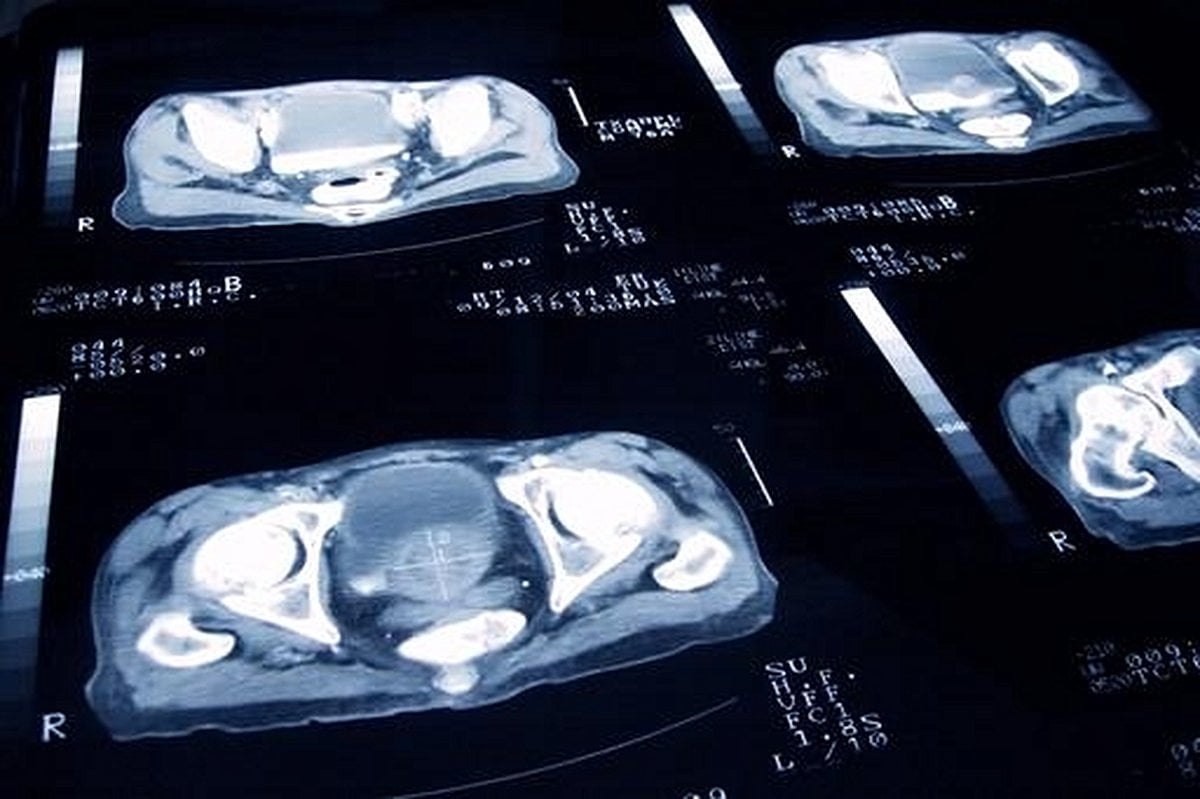

Prostate cancer is the most common cancer among men in the UK, with around 55,000 new cases diagnosed each year, according to Prostate Cancer UK and reporting from BBC. Yet, not every diagnosis means urgent surgery or radiotherapy. In fact, about one in four of these cases involve slow-growing cancers that are unlikely to ever cause harm. For these men, the best course of action may be what’s called “Active Surveillance”—a careful, non-invasive monitoring regime involving blood tests and scans, rather than immediate, potentially life-altering treatment.

However, a growing chorus of researchers, clinicians, and patient advocates are warning that thousands of men are being treated too soon, exposed unnecessarily to the risks of surgery or radiotherapy. The root of the problem, they say, is a set of “outdated” guidelines from the National Institute for Health and Care Excellence (NICE), the body responsible for setting national standards for NHS care. These guidelines, last updated in 2021, recommend Active Surveillance only for men in the lowest-risk category of prostate cancer. The NHS, however, updated its own guidance in 2024 to extend Active Surveillance to men in the second-lowest risk group, creating a confusing contradiction.

Why the confusion? NICE’s current guidelines recommend Active Surveillance only for those with the lowest-risk prostate cancer, where nine in ten men will have no signs of cancer progression within five years. But research now shows that even among those in the second-lowest risk group, eight in ten will remain stable over the same period. In other words, many men are being treated for cancers that would likely never have caused them harm.